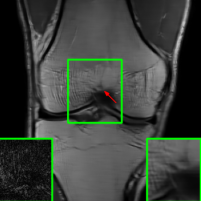

Figure 10 presents visual comparison of image reconstructions and their associated reconstruction errors within a closely examined region. Each image in the figure includes two inset panels in the bottom-left and bottom-right corners. The bottom-left inset panel, enclosed within a green bounding box, serves as a reference for the region of interest in the image. In contrast, the bottom-right inset panel depicts an error map in relation to the ground truth. Notably, our method stands out in its ability to capture more features from the original image, surpassing the performance of alternative methods (as also evident from the reported PSNR values).